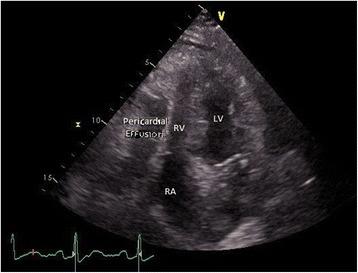

An otherwise healthy, 72-year-old Caucasian woman presented with complaints of progressive shoulder pain and dyspnoea on exertion. The blood test results showed elevated inflammation parameters and elevated hepatic transaminase levels. Radiologic examinations were carried out, and the computed tomography scan revealed a hepatomegaly and a chest X-ray showed evidence of a unilateral pleural effusion. A transthoracic echocardiography detected pericardial effusion with consecutive hemodynamic changes. Since it was considered that using ultrasound-guided pericardiocentesis could significantly increase the risk of liver injury due to hepatomegaly, a pericardial window was performed instead. Further investigation showed that our patient tested positive for an acute cytomegalovirus infection in the serologic tests. Laboratory findings included new evidence of immunoglobulin M seroconversion and high immunoglobulin G avidity, so we considered the possibility that a former cytomegalovirus infection may be coexisting with a new cytomegalovirus reinfection.

一名72岁的健康白种女性因进行性肩部疼痛和劳力性呼吸困难前来就诊。血液检查结果显示炎症参数升高和肝转氨酶水平升高。进行了放射学检查,计算机断层扫描显示肝肿大,胸部X线显示有单侧胸腔积液的迹象。经胸超声心动图检测到心包积液并伴有连续的血流动力学变化。由于认为超声引导下心包穿刺术可能因肝肿大而显著增加肝损伤风险,因此改为进行心包开窗术。进一步检查显示,我们的患者血清学检测巨细胞病毒急性感染呈阳性。实验室检查结果包括免疫球蛋白M血清转化的新证据和高免疫球蛋白G亲和力,因此我们考虑既往巨细胞病毒感染可能与新的巨细胞病毒再感染同时存在。